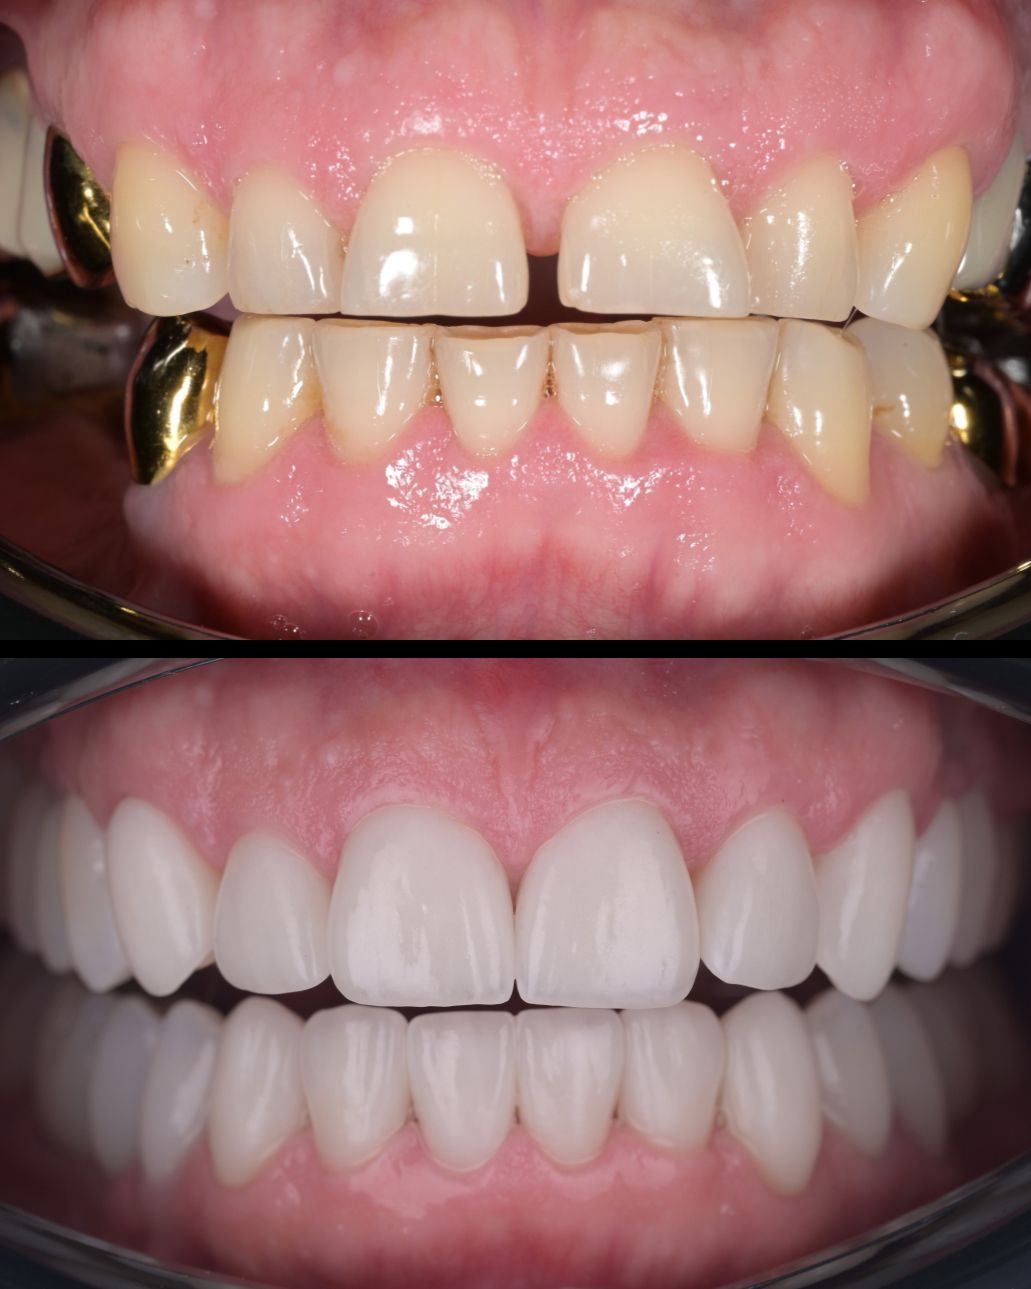

до и после

Хочу выразить огромную благодарность доктору Котоменкову Сергею Юрьевичу, превосходный доктор, уделяющий внимание деталям, профессионал своего дела. " С Вашей помощью, я восстановила не только свою улыбку , но и вновь обрела уверенность в себе. Оказывается посещение стоматолога ничуть не хуже визита к психологу. Идеально восстановил зону улыбки, сейчас и зубы свои не узнать, я в восторге. Спасибо за Ваш профессионализм и заботу. Однозначно рекомендую этого потрясающего доктора, тем кто хочет видеть здоровые и красивые зубы на все 1000%. Так же хочу сказать спасибо огромное прекрасному доктору хирургу-имплантологу Кушнаревой Анне Анатольевне за удаление 8-ого зуба, все прошло выше всех похвал, на следующий день и забыла что удалили зуб. И конечно ребятам ассистентам за их труд и внимательное отношение к пациенту.